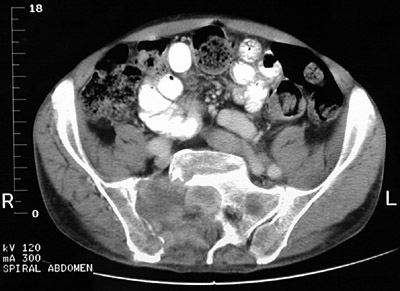

The large destructive mass arising in the region of the sacrum on the right is a chordoma. These locally destructive lesions most typically arise at the ends of the neuraxis--sacrococcygeal region and clivus (sella turcica).